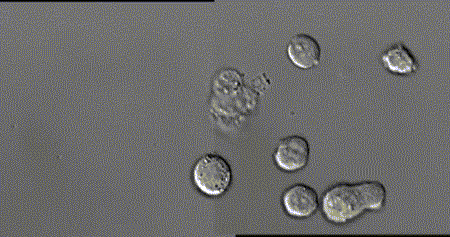

动画:什么是肽

人体的一切活性物质都是以肽的形式存在的。

过去人们对肽的认识还不够,现代随着科学的发展,人们开始认识肽、识别肽、研究肽、制作肽、服用肽,以适应现代健康的需要。